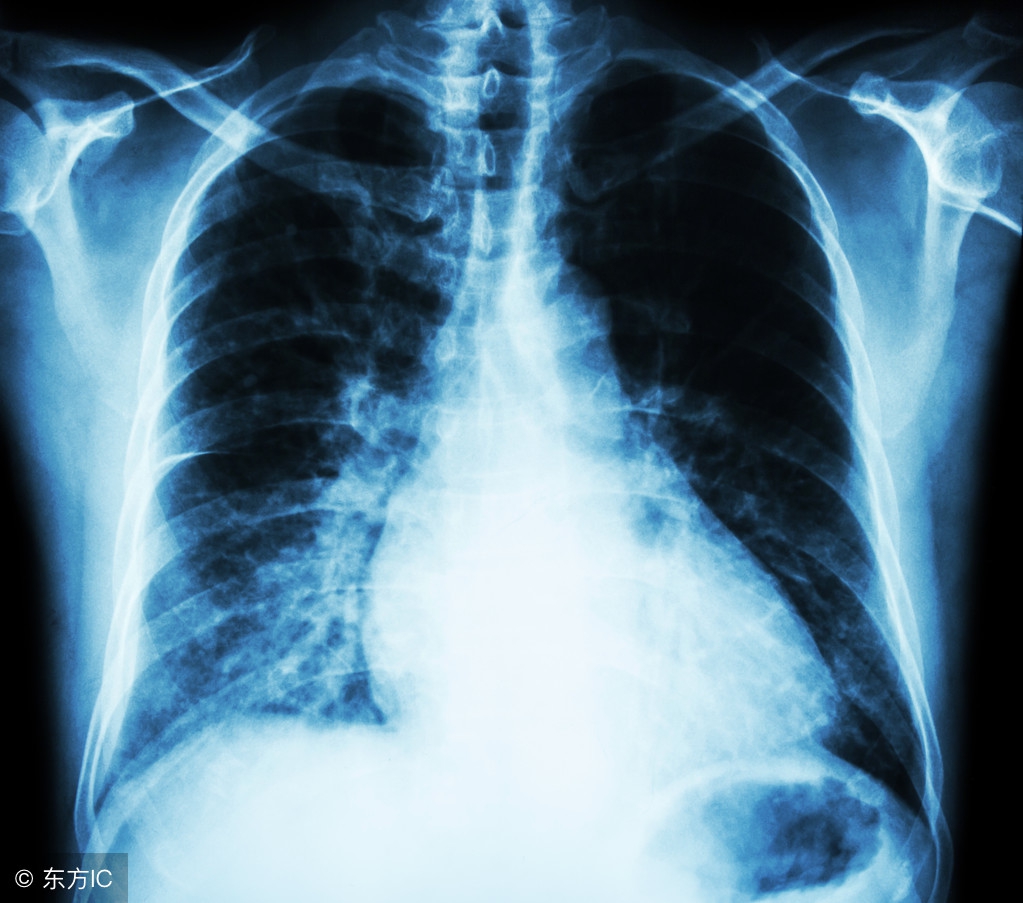

检查发现,张女士肺部肿瘤仅2厘米左右,但已出现了颅脑转移,这在临床上较为少见。虽然小病灶、大转移并不多见,但影像检查中,她肺部的病灶已呈现高密度影。“在影像学上,病灶最初为半透明的磨玻璃样,一般需要半年至一年时间,病情逐渐进展才会呈实质性病灶。”赵伟和主任提到。

据了解,张女士平时并没有定期体检的习惯。如果能够通过体检发现早期病灶,并进行定期随访,肿瘤可能就不会进展到晚期,多发转移从而失去手术根治的机会。“所以临床上医生会建议广大市民,定期进行胸部低剂量CT筛查,特别是40岁以上的高危人群,以便早期发现、及时治疗!”赵伟和主任建议。

《2017中国肿瘤登记年报》的统计显示,中国肺癌发病率、死亡率双率第一。定期体检非常重要,尤其是40岁以上人群,每年做一个低剂量CT,能够帮助发现早期肺癌,而手术治疗早期肺癌预后非常好,大多数不需要化疗。